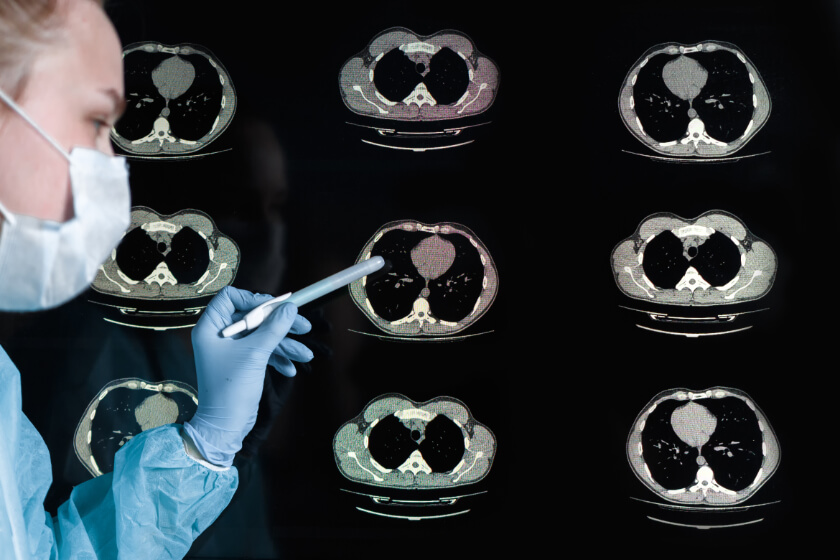

In a new study published in August of 2022, researchers found that the structural differences in airways between the genders might explain why the prevalence of COPD is rising so rapidly in women. The researchers looked at data gathered from the Genetic Epidemiology of COPD (COPD Gene) study, which included 10,000 participants who were current, former, and never smokers between the ages of 45 and 80. The participants were recruited from 21 clinical centers across the United States and all underwent chest CT scans.

Using the results of the CT scans, the researchers assessed each participant’s airway disease by measuring several metrics, including airway wall thickness and the diameter of the lumen. The researchers found that, of the 9,363 smokers in the study, men had thicker airway walls while women had a narrower lumen diameter. They also found that the women who had thicker airway walls or a narrower lumen diameter had poorer lung function, more shortness of breath, and worse overall survival. The female smokers also had a higher risk for mortality than did their male counterparts.

The research underscores the importance of considering gender when it comes to assessing patients’ risk for COPD and breathing problems associated with respiratory disease. CT scan can help detect signs of COPD, such as bronchial wall thickening, which can lead to early detection and treatment that slows the progression of COPD.